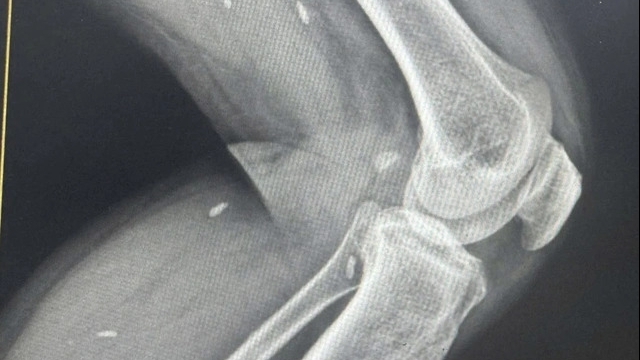

| Bệnh viện Nhi đồng 1 khẳng định không bao giờ có chuyện yêu cầu bệnh nhân hoặc gia đình phải đóng tiền trước rồi mới cấp cứu. (Ảnh: Hoàng Lan) |